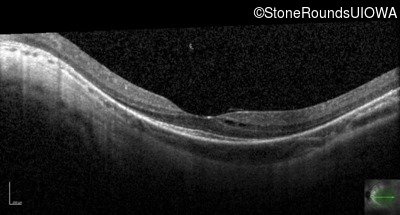

Optical Coherence Tomography - Right - 10/100 -1

Exemplar / OCT Stack

OCT Stack